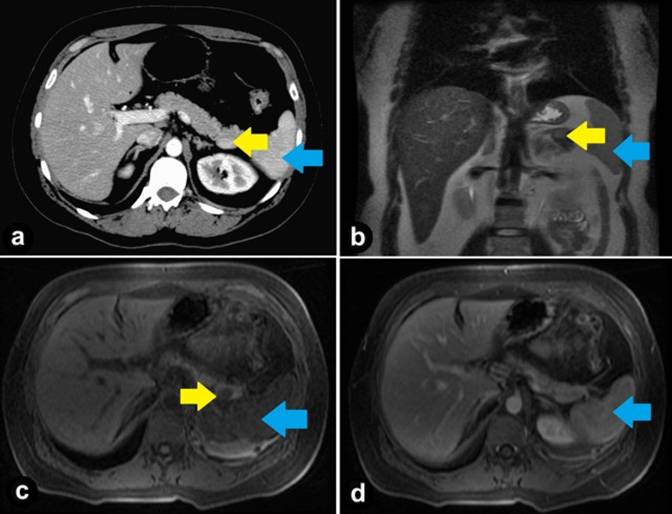

A 33-year-old lady presented with a three month history of dyspepsia. During evaluation, a 1.5 cm, homogenous, sharply defined lesion in the tail of the pancreas was seen on computed tomography (CT) scan of the abdomen and later confirmed by magnetic resonance imaging (MRI). The initial (pre-EUS) read on the CT and MRI suggested an enhancing intrapancreatic lesion concerning for a neuroendocrine tumor. Continued investigations included a negative Octreotide scan for pancreatic tumor localization. After being referred to our institution, review of radiological images suggested intrapancreatic accessory spleen since the signal intensity of the lesion was similar to the spleen on pre- and post-contrast CT and MRI sequences (Figure 1). Endosonography revealed a 1.5 cm, oval shaped, well-defined, homogeneous, hypoechoic lesion with similar echogenicity of the spleen (Figure 2). The pancreatic body and duct appeared normal. Two passes were made using a 22-guage needle for fine needle aspiration (FNA). The FNA showed normal pancreatic acinar tissue adjoining splenic pulp (Figure 3a) displaying extramedullary hematopoiesis (Figure 3b) and prominent vascularity (Figure 3c). Immunostaining with CD8 highlighted the sinus endothelial cells (Figure 3d) confirming diagnosis of intra-pancreatic accessory spleen.

Figure 1. a. Contrast-enhanced axial CT Scan showing intra-pancreatic lesion in the tail of the pancreas isoattenuating compared to spleen. b. Coronal T2-haste MR image showing intra-pancreatic accessory spleen with signal intensity similar to that of the spleen. c. Axial pre-contrast T1-weighted MRI with fat saturation showing hypointense signal of intrapancreatic accessory spleen relative to the pancreas. d. Axial gadolinium T1-weighted MRI, portovenous phase (notice that intrapancreatic accessory spleen becomes homogenously isointense relative to surrounding pancreatic parenchyma, nearly obscuring the lesion). Intrapancreatic accessory spleen (yellow arrow); spleen (blue arrow). |